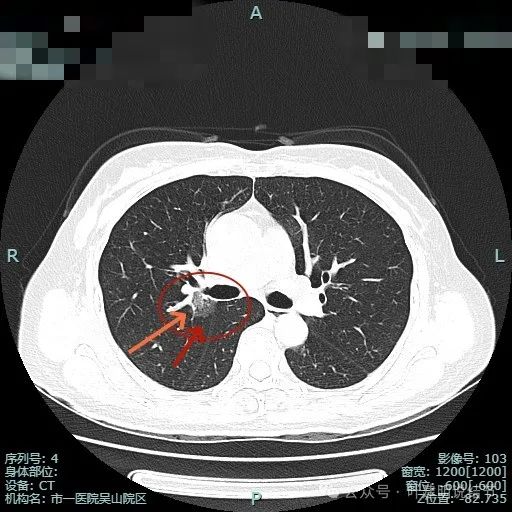

病灶1密度已经淡了;病灶2刚好位于上叶支气管发现后段支气管处,与支气管壁没显著间隙。

病灶1已经淡,且靠降主动脉近;病灶2密度其实也不纯,灶内有微小血管穿行,边缘侧有血管贴边,与支气管管壁间没有间隙。

病灶1边缘部分的样子;病灶表面欠光滑,有血管贴边。整体轮廓与边界清楚。

病灶2血管与病灶间没有间隙,表面浅分叶,并贴着斜裂。

斜裂略有牵拉向病灶,灶内密度稍不均,边缘有短细小毛刺征。